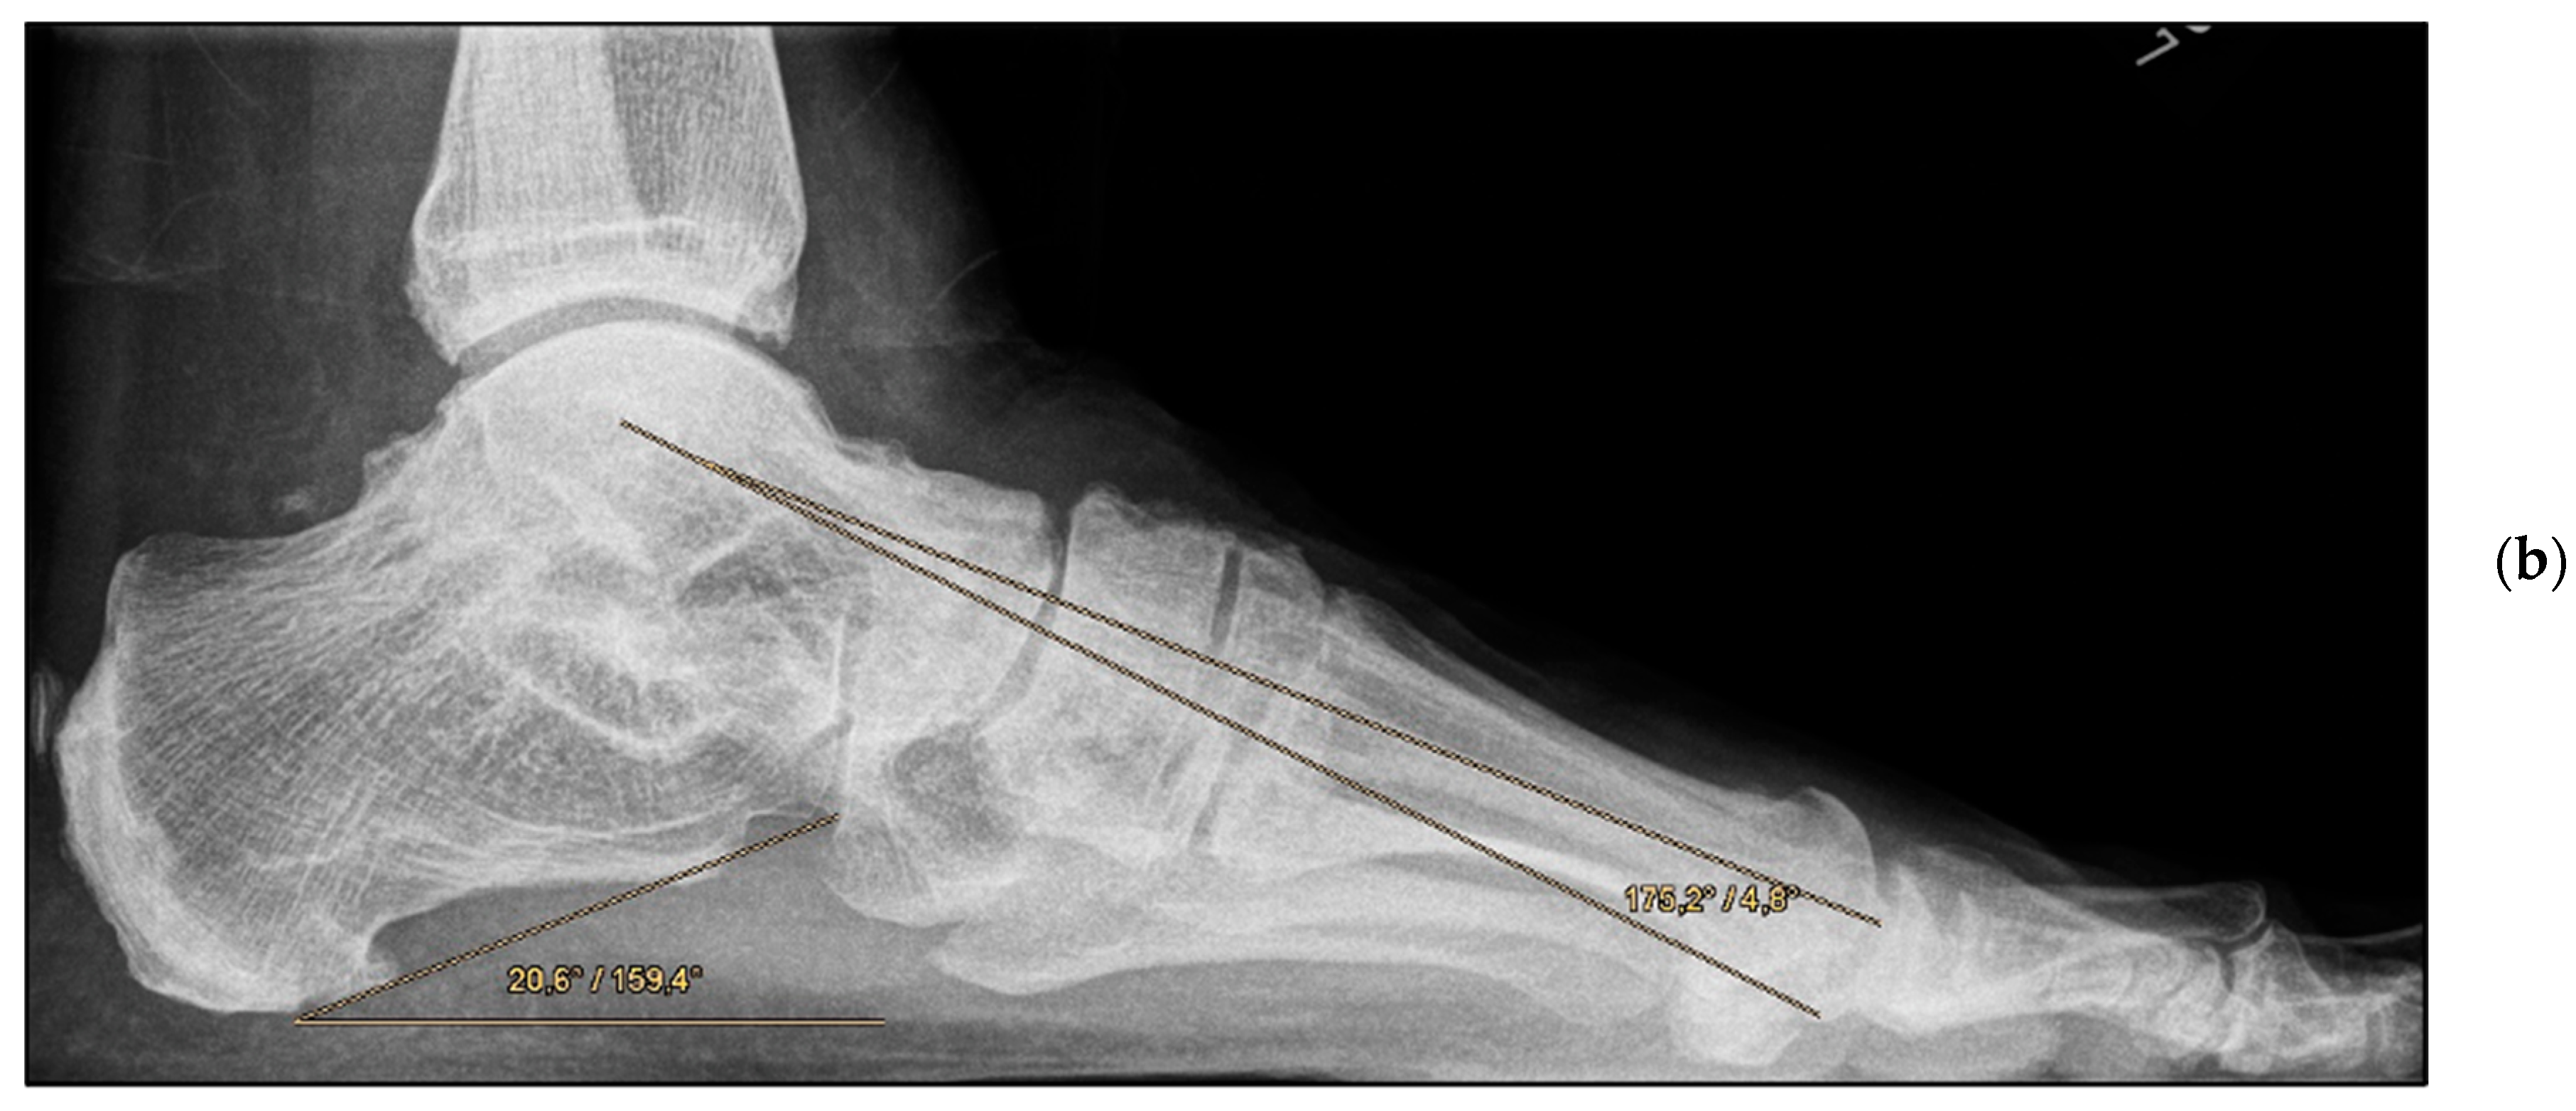

Pre- and post-operative radiographic findings of double arthrodesis, left foot. (a) Lateral view pre-operative, (b) lateral view post-operative after implant removal.

Double Arthrodesis (Group B). Firstly, subtalar arthrodesis was performed via a lateral subtalar approach. Care was taken to ensure thorough resection of the articular surfaces and extensive release to achieve adequate correction of the valgus deformity and avoid the development of pseudarthrosis. Here, too, the insertion of autologous cancellous bone was considered obligatory. Fixation was achieved by means of two percutaneously inserted lag screws (diameter of 6.5 mm). The subsequent talonavicular arthrodesis was performed as previously described (Figure 4a,b and Figure 5a,b).

The mean FFI-D was 33.9 (group A: 34.5; group B: 33.5); the mean SF-12 physical component summary was 43.13 (group A: 40.9; group B: 44.9); and the mean SF-12 mental component summary was 43.13 (group A: 40.9; group B: 44.9) (Table 2). No significant differences were observed between the groups. The post-operative results demonstrated that the angles (talometatarsal and talocalcaneal in the anteroposterior and lateral view) were largely comparable (Table 3). Only the lateral talocalcaneal angle showed a significant difference between the groups (group A: 50.5°; group B: 46.1°; p = 0.047), norm value < 50° [21]. All reconstructed angles were also compared with the clinical scores. No correlation could be found either in the respective group or with all study patients together (e.g., FFI-D versus post-operative dorsal talometatarsal angle, r = 0.023).

Encouragingly, the angles were shown to be comparable to the post-operative values otherwise obtained in joint-preserving procedures in young adults [16]. The talo–first metatarsal angle on lateral view, the so-called Meary’s angle, represents one of the most important radiological criteria regarding the assessment of flatfoot deformity. Thus, in the present study, a moderate-to-severe deformity could be converted into a physiological configuration or at most a mild deformity in all patients, irrespective of the group allocation [31].